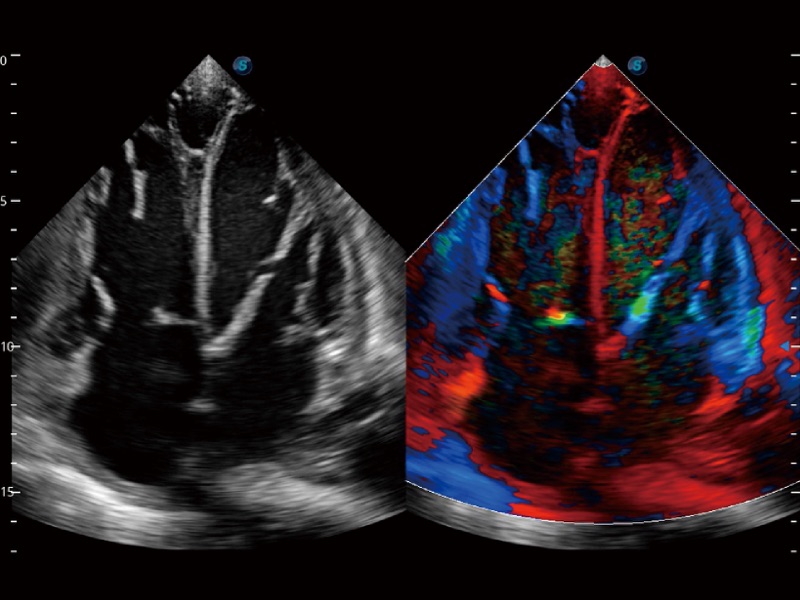

• 心血管应用

支持运动和药物负荷协议、多心动周期存储选择,为临床观察心肌负荷状态下的室壁节段运动、评估心肌缺血状态提供更多的解决方案。

• 心肌定量分析 MQA

通过心肌识别技术和二维斑点追踪技术相结合,计算心肌各节段的应变应变率、速度、位移并以曲线图显示,实现整体或者局部心肌定量分析。同时可呈现牛眼图直观和准确诊断心肌的运动情况。